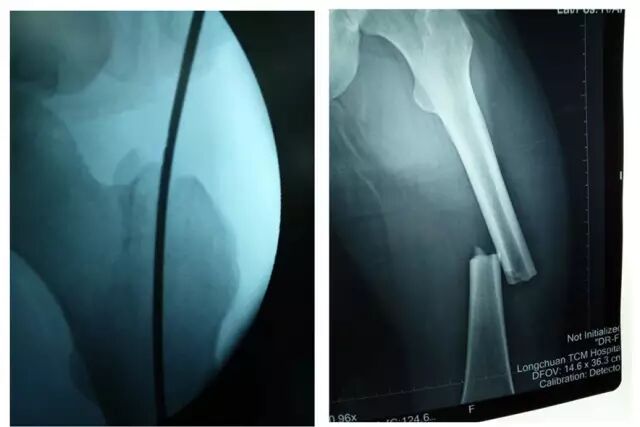

中医院骨一科2016年8月21日由外院转入一位男性患者张某,23岁,入院诊断为左股骨中段骨折、先天性聋哑(智力障碍)。完善各项检查后,在麻醉科袁文强主任、黄惠球副主任医师,骨一科骆新明主任、乐家忠、黄锋医师共同配合下,于8月25日行左股骨闭合复位、小切口开窗交锁髓内钉内固定术,手术顺利完成,病人术后两天能下地扶拐活动行走,术后恢复良好。

↑图:术前拍片

↑图:术后拍片